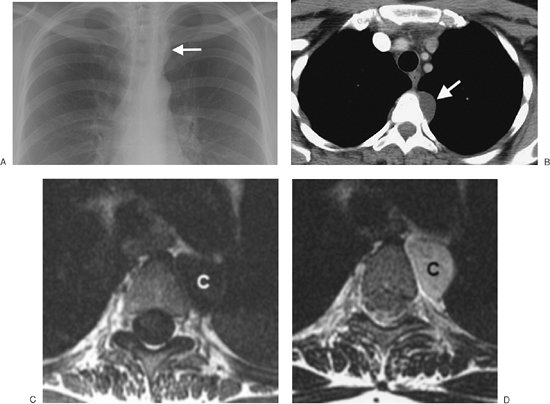

FIGURE 6-29. Bronchogenic cyst. A: PA chest radiograph shows an abnormal left superior mediastinal contour (arrow). B: CT scan shows a nonenhancing left paraspinal mass of homogeneous fluid attenuation with an imperceptible wall (arrow). C: T1-weighted MRI shows the mass to have low signal intensity (C). D: The mass has high signal intensity on T2-weighted MRI (C), consistent with a cyst.